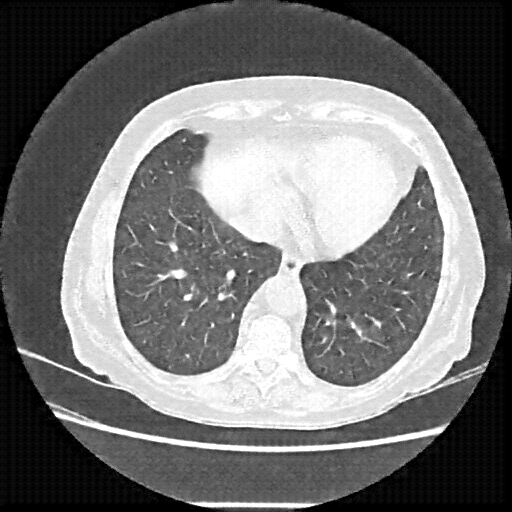

Original NATIVE CT scan (input)

Full window (WL 1023.5, WW 4095 β†’ Low βˆ’1024, High +3071)

Lung window (WL -600, WW 1500 β†’ Low βˆ’1350, High +150)

Mediastinum window (WL 40, WW 400 β†’ Low βˆ’160, High +240)